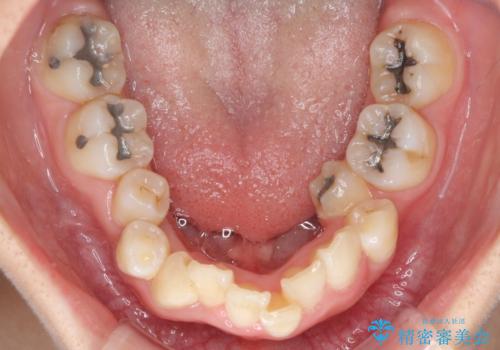

- 内側に倒れ込んだ歯や下の前歯が隠れてしまうほどの咬み合わせを改善したいとのことで来院された患者様です。

下顎の叢生を解消するために抜歯が必要であり、奥歯の咬み合わせや口元の印象から、上顎も同様に抜歯と判断し、上下左右の第1小臼歯4本抜歯してワイヤー装置にて矯正治療を行うこととしました。